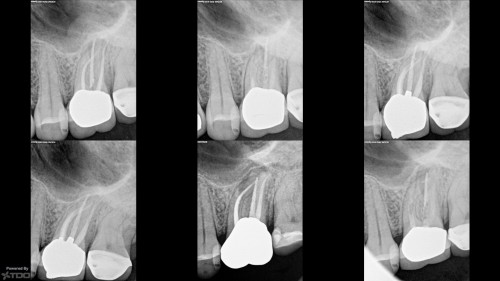

9yo girl, #9 ankylosis and discoloration

By Brandon Seto / August 2, 2018

Dear colleagues, I posted this to the AAE forum, and I’m hoping for input from […]

9yo girl, ankylosis and discoloration #9

Dear colleagues, I just posted this to the AAE forum, and I’m hoping TDO’ers could […]